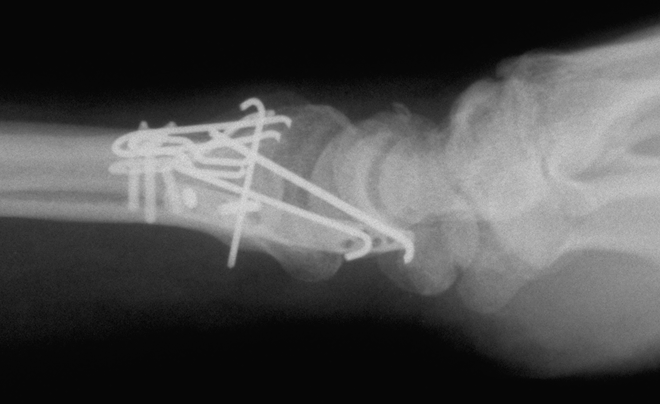

Case 1 Postop